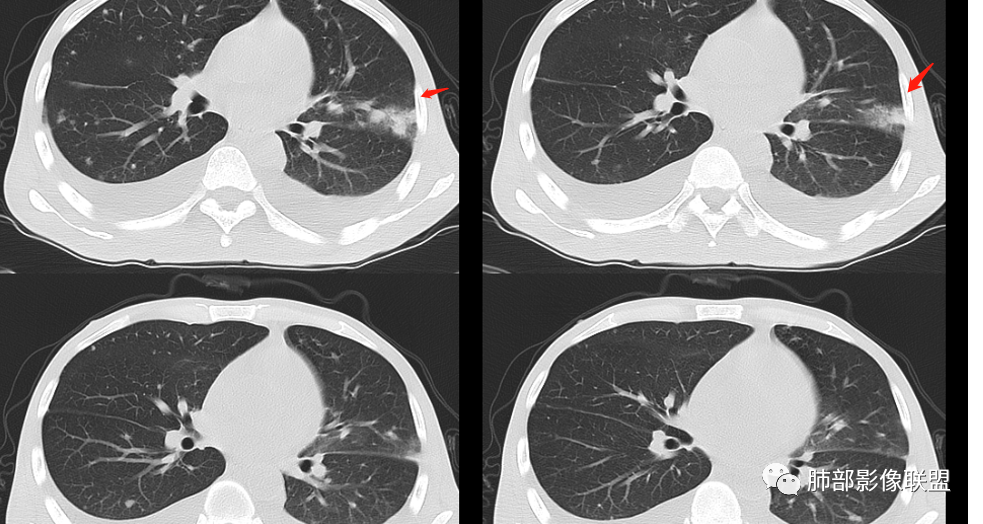

年轻男性,肠癌术后,目前间断有发热,胸部CT提示双肺散在结节影,左肺上叶近胸膜处可见以不规则密度增高影,边界不清,周边可见磨玻璃影,附近支气管壁增厚,支气管引流,附近可见卫星结节,内有空洞,考虑二元,转移瘤合并结核

青年男性,既往结肠癌病史,卡培他滨加贝伐单抗治疗,末次化疗时间2019年9月 有肠梗阻病史。低热,血常规基本正常低蛋白血症,血糖偏高,肾功能衰竭,CT提示双侧胸腔积液,双肺散在结节影,胸膜下多见,左上肺密度增高影,第一个选择我还是考虑感染。结核,真菌?第二恶性肿瘤,常规考虑转移。很好奇这病咋确诊

青年男性,恶性肿瘤化疗病史,透析病史,血糖高,提示糖尿病。白细胞不高,伴发热,贫血,双侧胸腔积液,左肺上叶片状高密度影,边缘可见磨玻璃密度,临近支气管管壁增厚,内可见空泡,双肺另多发小结节,随机分布,部分结节周围有晕,一元解释,考虑感染性病变,真菌可能大

左肺上叶上舌段平行胸膜下斑片并相互融合成小片状实变影,边缘见模糊晕征,余两肺叶外周近胸膜下随机分布小斑点,斑片影,部分小结节样及周围小晕征,考虑隐球菌感染;心室腔低符合贫血表现;双侧胸腔少量积液。

飞鹰行动:

青年男性,有恶性肿瘤化疗病史,血糖高。发热,贫血,双侧胸腔积液,左肺上叶片状高密度影,边缘可见磨玻璃密度,临近支气管管壁增厚,内可见空泡及小空洞,未见明显液平面,双肺另多发小结节,随机分布,部分结节周围有晕,考虑血道来源感染性病变,肺克,奴卡,大肠杆菌,真菌可能。

青年男性,有结肠癌手术及化疗病史,因腹胀腹疼疑诊肠梗阻入院,有肠梗阻病史。间断发热。肾功能明显异常,贫血,白细胞不高,降钙素原升高明显,低蛋白血症。胸部CT双肺野散在结节影,沿支气管血管束分布,周围有晕,形态不规则,边界有不清,有清楚,左上肺舌段靠近胸膜下楔形实变影,边缘模糊,周围磨玻璃影,双侧中量胸腔积液,心腔内有低密度影,考虑贫血所致。患者存在抵抗力低下,降钙素原高,首选考虑感染性病变,肺克?不排除二元论结肠癌转移并左肺炎性病变。胸腔积液可能与低蛋白血症和肾功能不全有关。

青年男性,恶性肿瘤化疗病史,血糖偏高,白细胞不高,伴发热,贫血,1月左输尿管梗阻(肠癌复发所致?),当时ct未见异常,3月入院双肺随机分布结节,左肺舌段片状实变,边缘可见磨玻璃密度,一元考虑感染性病变(真菌?),转移待排。

2.双肺散在不规则小片状影及结节影,部分可见磨玻璃晕。结节影边界较清楚。左肺片影边界不清,范围较大,支气管相关,支气管壁增厚不明显,病灶内见液化空洞。